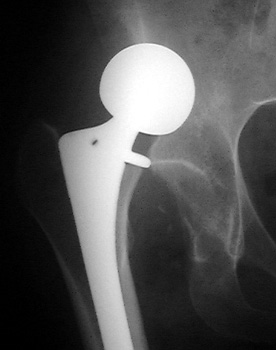

Dislocated total hip replacement